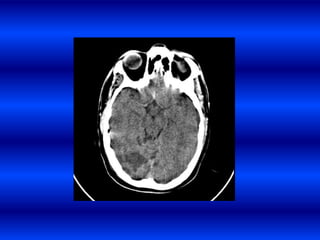

EXPANSIÓN TEMPRANA

Pte masculino, raza negra,

APP de HTA que sufre una

HIP subcortical derecha

que en los primeros

80mtos presenta cefalea,

disartria ligera y

hemiparesía izquierda en

la segunda TAC hay un

deterioro progresivo de la

conciencia , midriasis

derecha por hernia uncal y

apertura a ventrículos

laterales.

• 34.

EXPANSIÓN TEMPRANA DE HIC. Ptemasculino, raza negra, APP de HTA que sufre una HIP subcortical derecha que en los primeros 80mtos presenta cefalea, disartria ligera y hemiparesía izquierda en la segunda TAC hay un deterioro progresivo de la conciencia , midriasis derecha por hernia uncal y apertura a ventrículos laterales.